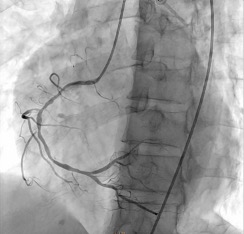

Relevant Catheterization Findings

Left main artery is a 3.0 mm vessel without disease. Left anterior descending artery is a 2.5 mm vessel with tightest lesion of 70-80% tubular stenosis at the mid segment and left circumflex artery is a 2.5 mm vessel with a 80-90% tubular stenosis at the midsegment. Right coronary artery is a is a 2.5 mm diffusely diseased vessel with tightest lesion of 80-90% at the proximal. The AV continuation is a 2.0 mm vessel with luminal irregularities.